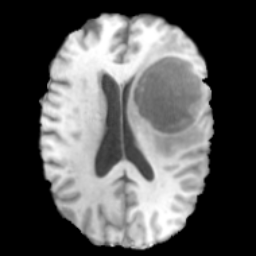

Brain MRI

We also evaluate our method on the BraTS-Reg (Baheti et al. 2021) dataset, which provides pre-operative and follow-up MRI scans for patients with diffuse glioma. The dataset includes multimodal MRI sequences (T1, T2, FLAIR, and T1 contrast-enhanced) collected longitudinally for each subject. To mitigate inter-scan variability caused by different acquisition protocols, histogram standardization (Nyul, Udupa, and Zhang 2000) is first applied to the pre-operative and follow-up T1 and T2 scans. We then perform Z-normalization, rescale the intensity to the range, and crop the scans to a resolution of . The pre-operative and follow-up scans are rigidly aligned using the SimpleITK registration framework (Yaniv et al. 2018). For experiments, 160 subjects in BraTS-Reg are split into training and testing sets with a 7:3 ratio and the central eleven slices are extracted to form a dataset with 1232 training pairs and 528 testing pairs.

4.5 Experiment Results on Brain MRI

To further demonstrate the effectiveness of TraceTrans, we additionally evaluated the model on Brain MRI dataset. The quantitative results are shown in Table 2 and TraceTrans performs best in SSIM, MAE, NMI and slightly worse than MUNIT in PSNR. Since the difference between TraceTrans and MUNIT on PSNR is less than 5% of either standard deviation, then this difference is negligible. TraceTrans shows significant SSIM improvement while matching MUNIT’s PSNR and achieving the lowest MAE, demonstrating balanced excellence in both structural and textural translation. Qualitative results are illustrated in the second row of Figure 4, the image generated by our model is visually best similar to the reference image.